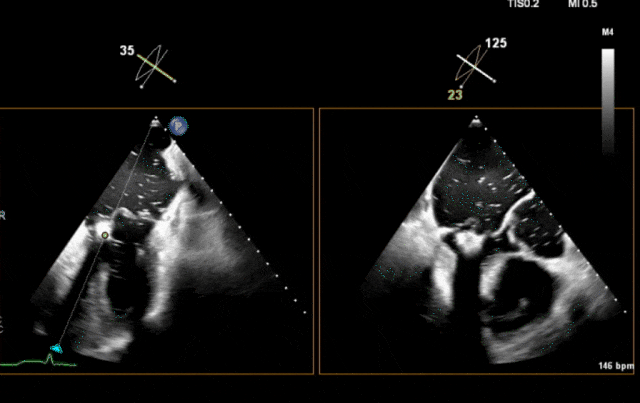

心脏超声示左室增大,二尖瓣2、3区脱垂伴重度反流(腱索断裂),Carpentier分型Ⅱ型,典型Barlow综合征表现;二尖瓣开放面积5.0cm²,3区瓣环内径31mm,前叶长22mm、后叶17mm,前叶收缩期关闭瓣体部分呈拱形突向左房腔,瓣膜游离缘对合欠佳,可见腱索断裂,长度9mm;2区瓣环内径32mm,前叶长22mm、后叶10mm,前后叶均可脱垂;三尖瓣重度反流。CDFI示瓣口重度偏心性反流,反流束沿主动脉后壁走行,肺静脉收缩期可见反向频谱。

术前瓣叶

图片

术前3D